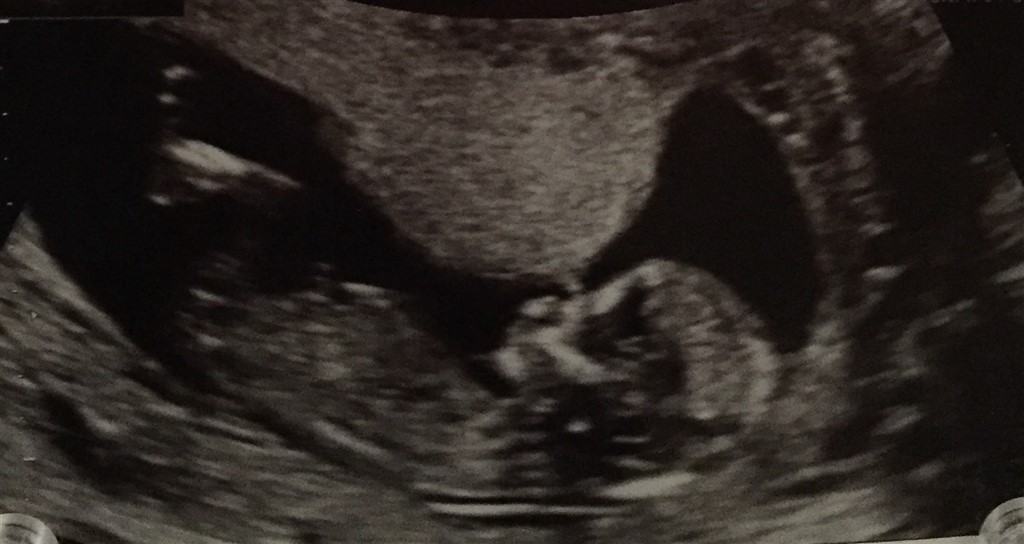

NF også gennemført her med så fine tal

Vedhæftede fotos (klik for at se i fuld størrelse)